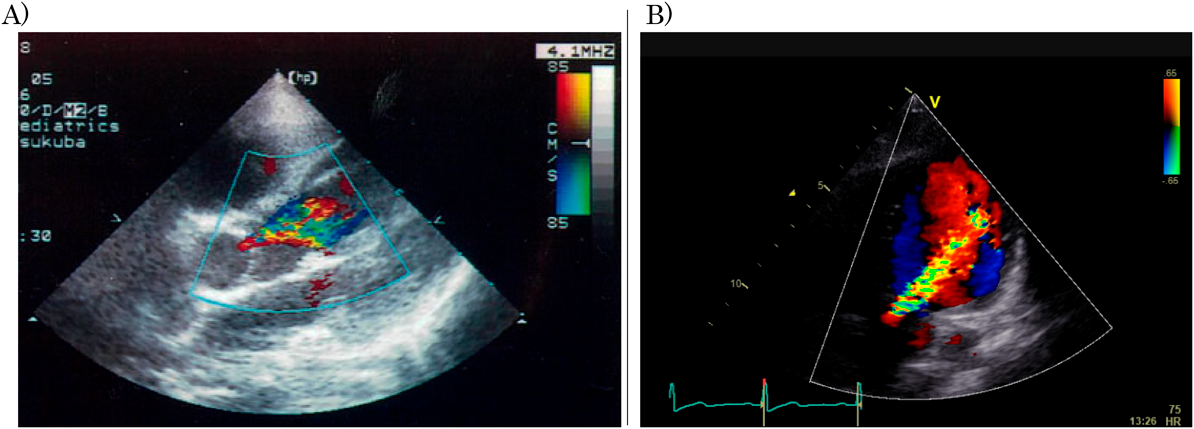

Fig. 1 Color Doppler echocardiograms of case 2

A) Color Doppler echocardiogram of case 2 on admission, showing moderate aortic regurgitation (AR) on the 5-chamber view. Left ventricular end-diastolic dimension (LVEDD) and ejection fraction (LVEF) were 34.6 mm (110.2%n) and 67.1%, respectively. B) Color Doppler echocardiogram of case 2 recorded 13 years after the onset of rheumatic fever, showing AR was increased. LVEDD, LVEF, pressure half time (PHT) and vena contracta (VC) were 45.7 mm (103%n), 66%, 544.4msec and 0.46 mm, respectively. This patient underwent aortic valve replacement.